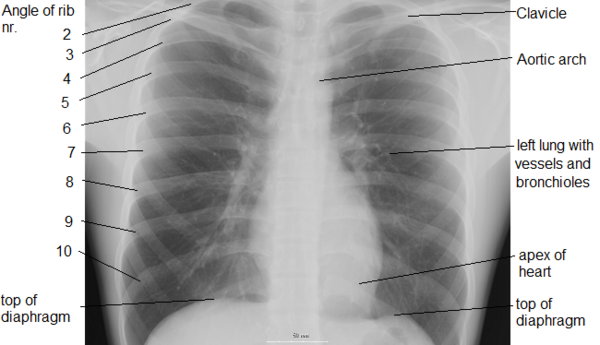

Грудная полость (лат. cavum thoracis) — анатомическое пространство, ограниченное внутренней поверхностью грудной клетки и верхней поверхностью диафрагмы. Стенки грудной полости выстилает внутригрудная фасция (лат. fascia endothoracica). Центральные отделы грудной полости заняты средостением, по бокам от которого расположены лёгкие. Лёгкие со всех сторон окружены щелевидными плевральными полостями, сформированными висцеральным (внутренним) и париетальным (наружным) листками плевры.